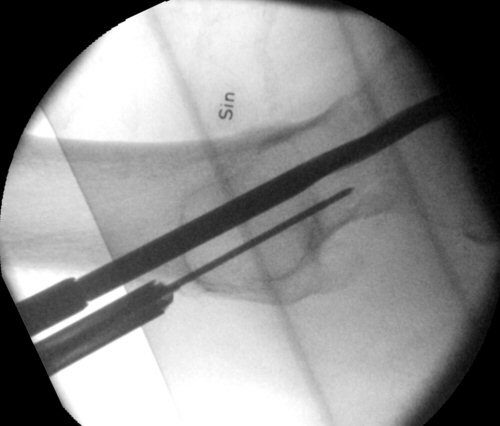

- Spara röntgenbilder.

Kontrollröntgen med LIH-spikar i bra lägen: parallella, lagom långt inslagna, lagom långa, nära distala resp. dorsala kortex och med låsfjädrar i korrekta riktningar